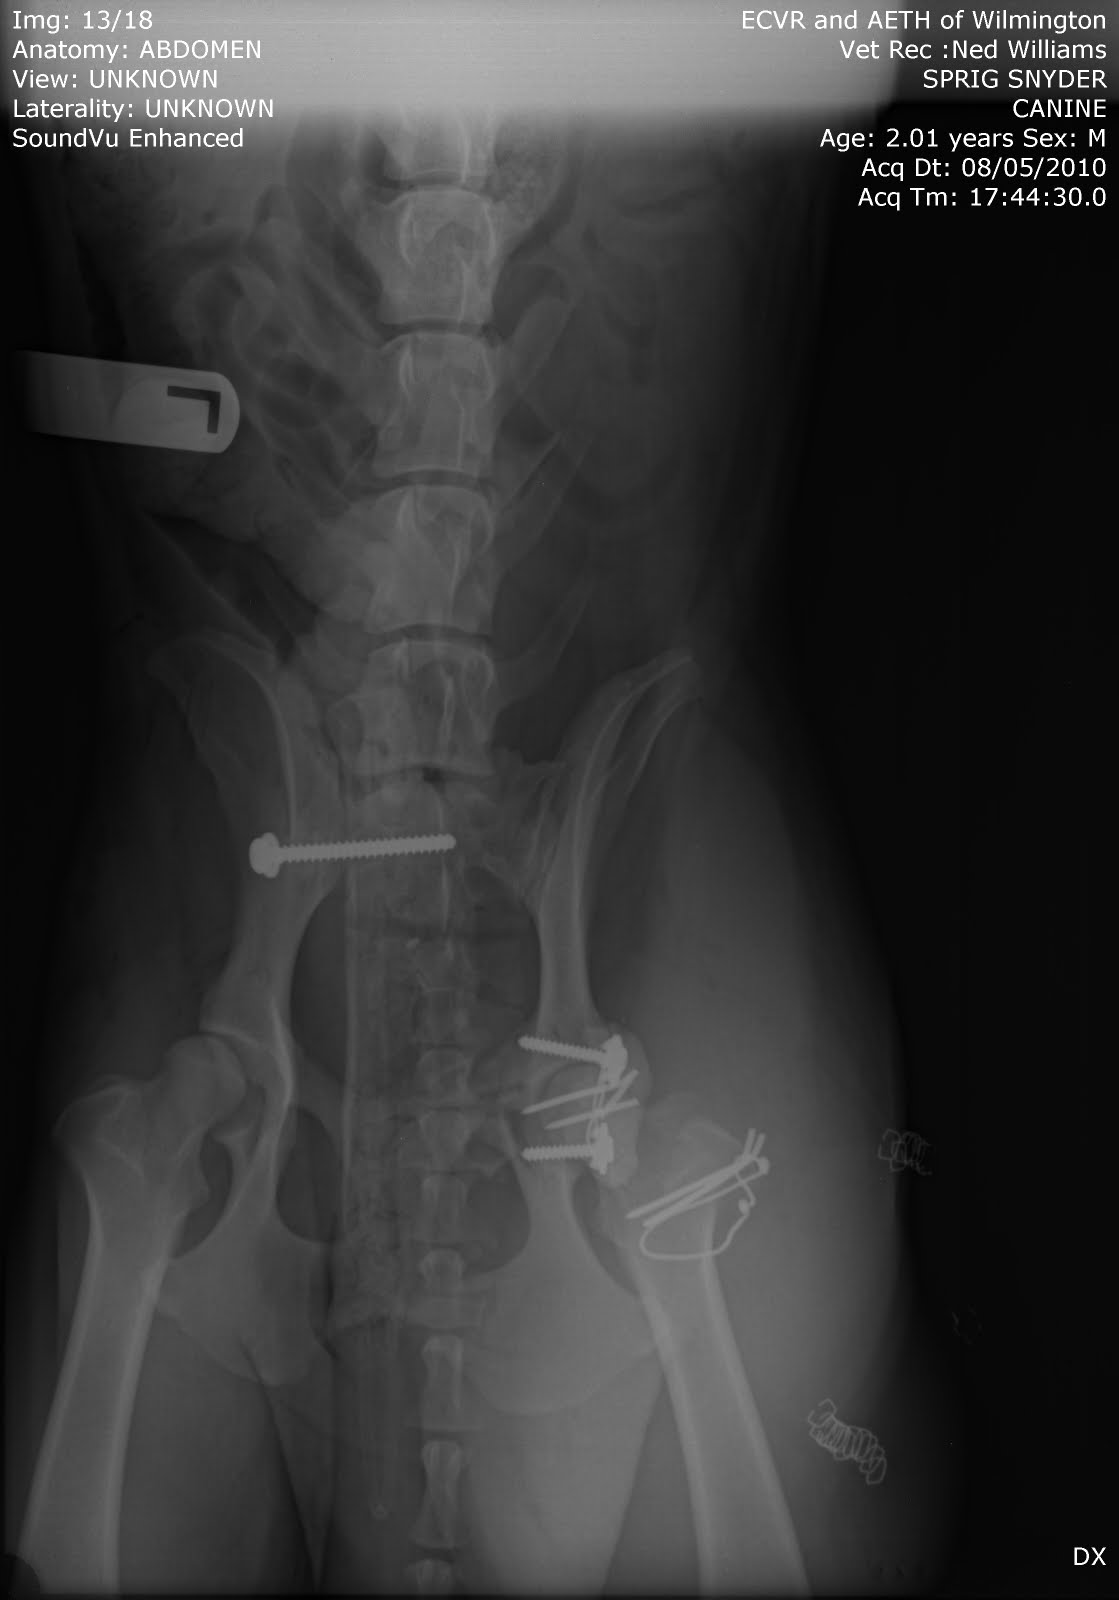

After right hip didn't hold, notice how the screw in his left hip has moved

Right hip still in place, screw in left hip not moving any further but you can see the infection in his right leg just under the wires in his femur.